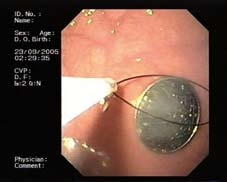

Endoskopické vyšetření horního zažívacího traktu u dětí je třeba provést v celkové anestezii, v případě CT se zajištěním dýchacích cest endotracheální intubací, abychom zabránili vdechnutí (aspiraci). Výkon by měl být prováděn na dobře vybaveném endoskopickém pracovišti. Vedle zkušeného endoskopisty a anesteziologa tu hraje velkou roli i asistence zkušené endoskopické sestry. K extrakci CT se používají různá akcesoria - kličky, kleště, košíky, tripody (obr. 2-4). V případě extrakce ostrých předmětů je vhodné použít overtube (kryt, do kterého je ostré CT vzato, aby nedošlo k poranění stěn zažívacího traktu) (obr. 5).